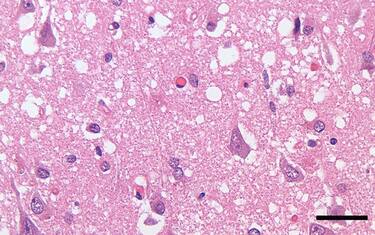

Malattia del cervo zombie, cosa sono i prioni e come causano il morbo Salute e Benessere Si tratta di proteine “anomale” in grado di trasmettere la loro irregolarità alle proteine sane... 27 feb - 12:44